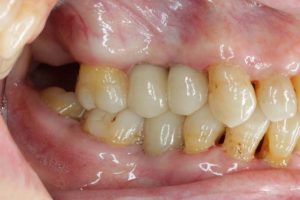

- 術前

- 術後

- インプラント手術直後のレントゲン

長い間お疲れさまでした。この方は、前歯に審美的なインプラントを入れるため、抜歯後4ヶ月待ち、仮歯で歯肉が成熟するのを数が月待っていたりした為に、完成まで時間がかかってしまいました。

虫歯治療などは短期間で終えることができるのですが、歯ぐきをいじり出すとどうしても治癒期間が必要となり長くなってしまいます。それもこれも奇麗な仕上がりのために欠くことのできないものです。何卒ご容赦を!